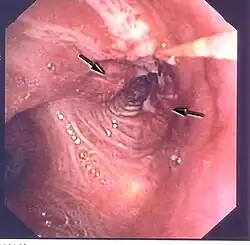

Diagnostik

Eine wichtige Rolle bei der Diagnose eines Bronchialkarzinoms spielen die bildgebenden Verfahren. So sind das Röntgen des Thorax in zwei Ebenen und die Computertomografie (CT) des Thorax die Mittel der Wahl zum Erkennen und Lokalisieren von Bronchialkarzinomen. Die Positronen-Emissions-Tomographie (PET) kann darüber hinaus zum Aufspüren von Fernmetastasen verwendet werden. Die Bronchoskopie wird zur Gewinnung von Gewebeproben für die histologische Beurteilung des Tumors herangezogen. In der Labordiagnostik können die Tumormarker Neuronenspezifische Enolase (NSE) und CYFRA 21-1 zur Diagnosestellung mitverwendet werden, die Ergebnisse sind aber nicht sicher.

„Okkult“ ist ein Bronchialkarzinom, wenn der Ursprungstumor nicht gefunden wurde und die Diagnose nur z. B. durch einen zytologischen Befund gestellt wurde. Die Diagnostik wird sich dann meist auf eine Röntgenaufnahme des Thorax und eine Bronchoskopie beschränken. Kurzfristige Nachuntersuchungen (z. B. mittels CT) sind erforderlich, da sich der Primärtumor im Verlauf der Erkrankung doch noch zeigen kann.

Tumoren, die auf diese Weise entdeckt worden sind, befinden sich meist noch in einem frühen Stadium. Durch eine rechtzeitige Operation und vollständige chirurgische Entfernung sind diese Tumoren heilbar. Falls der Primärtumor gefunden werden kann, gestaltet sich die weitere Behandlung abhängig vom genauen Tumorstadium des Patienten.

Bei wenigen als geeignet angesehenen Patienten wurde eine endoskopische Phototherapie mit einem Hämatoporphyrin-Derivat als mögliche Alternative zur chirurgischen Entfernung vorgeschlagen. Diese Behandlung, die derzeit in klinischer Erprobung ist, scheint am wirksamsten für sehr früh entdeckte zentral sitzende Tumoren zu sein, die sich weniger als einen Zentimeter in den Bronchus hinein erstrecken. Ob diese Behandlungsform wirklich geeignet ist, Lungenkrebs im frühen Stadium zu heilen, muss aber noch besser erforscht werden.